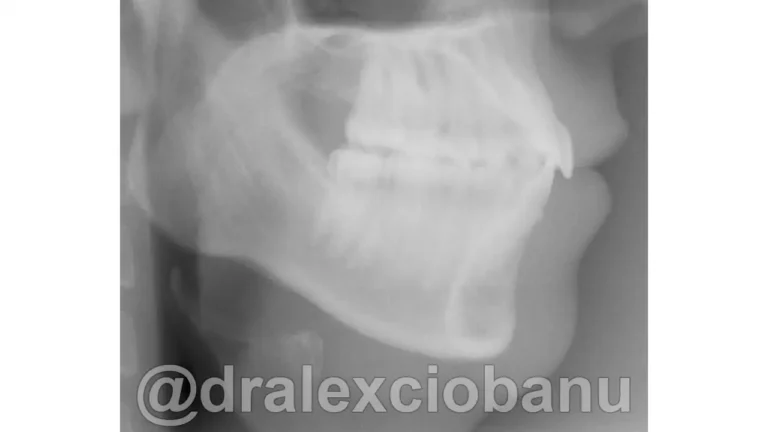

I brackets linguali possono allineare sia le corone che le radici dei denti, in modo che siano perfettamente posizionati l’uno accanto all’altro in posizione corretta. È spesso difficile ottenere questo posizionamento utilizzando gli allineatori rimovibili, specialmente quando si tratta di correggere le rotazioni dei canini. I brackets linguali fissi possono posizionare perfettamente i canini e i denti anteriori nella posizione corretta, come mostrato nella radiografia orto panoramica al termine della terapia.

Abbiamo corretto il morso ed ottenuto il perfetto allineamento dei denti.

Tempo totale di trattamento: 10 mesi.